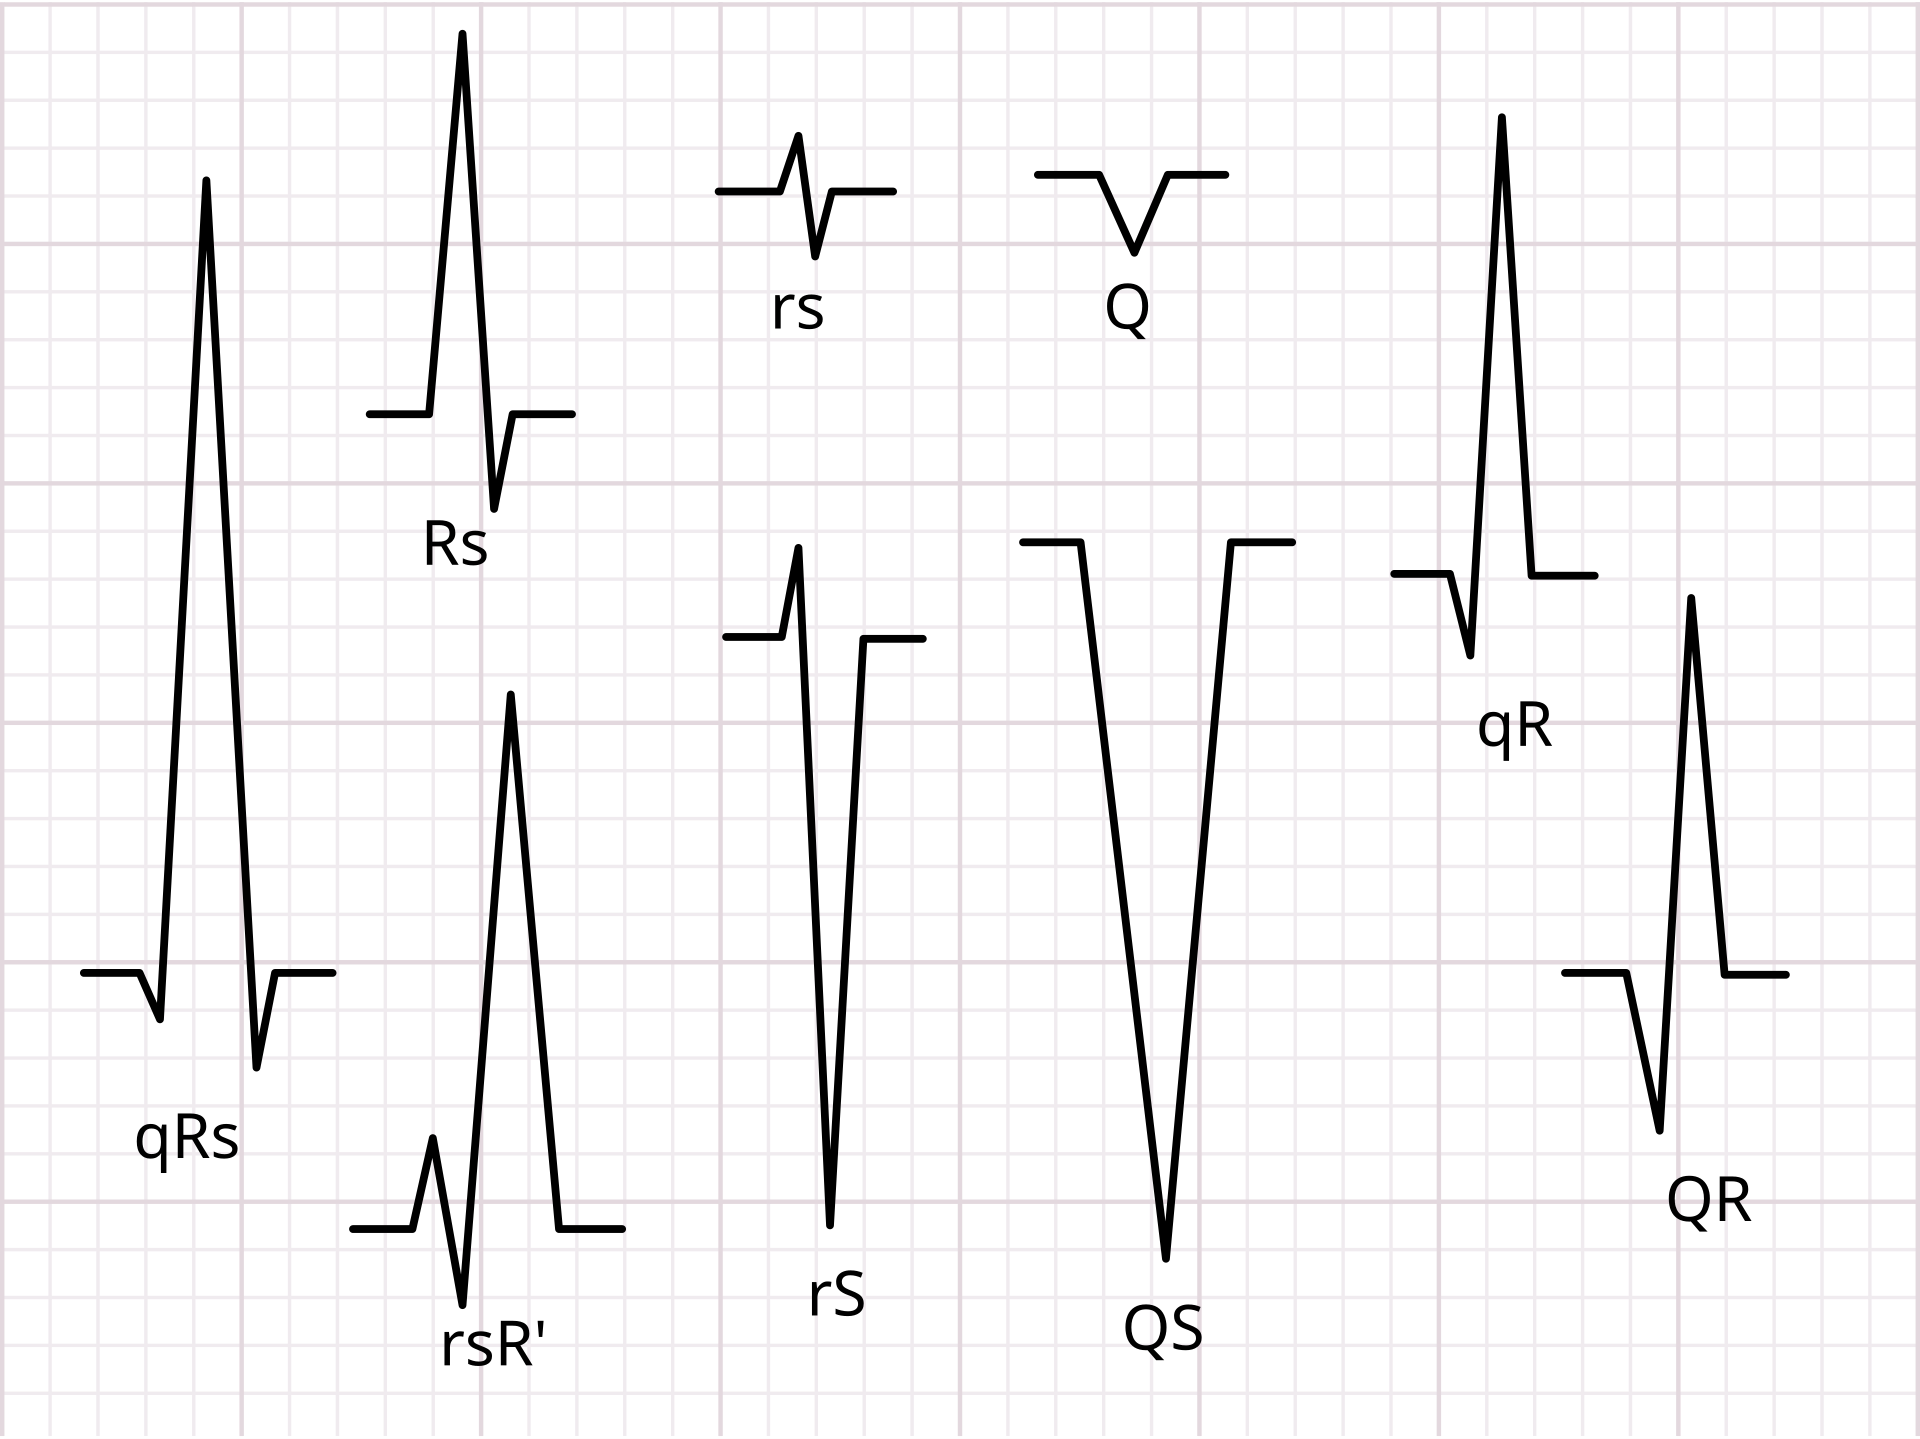

正常心电图的一个周期中一定可以依次观察到三组波形:P波、QRS波群与T波,偶尔可在T波后见一较小的U波。P波为外观较圆、幅度较小的波形,代表心房去极化,在肢体导联中振幅通常在0.1~0.3mV之间。P波之后的第一个负向波称为Q波,第一个正向波称为R波,R波之后出现的负向波称为S波,三者共同组成QRS波群。QRS波群为时程短、振幅大、外观呈尖峰状的波形,代表心室去极化,在肢体导联中振幅通常在1.0~1.5mV之间。QRS波群之后出现的大小中等、基底较宽的波形为T波,代表心室复极化,在肢体导联中振幅通常在0.2~0.3mV之间。有的时候也可在T波后观察到一个较小的正向波,称为U波,其产生机制不完全清楚,在某些疾病状态下可见增大,不过也可在正常人中出现。

顺带一提,并不是所有情况下都能观察到典型的QRS三个波都存在的QRS波群。下面是一些QRS波的形态示例,至于属于正常现象还是异常现象,需要视具体情况分析。